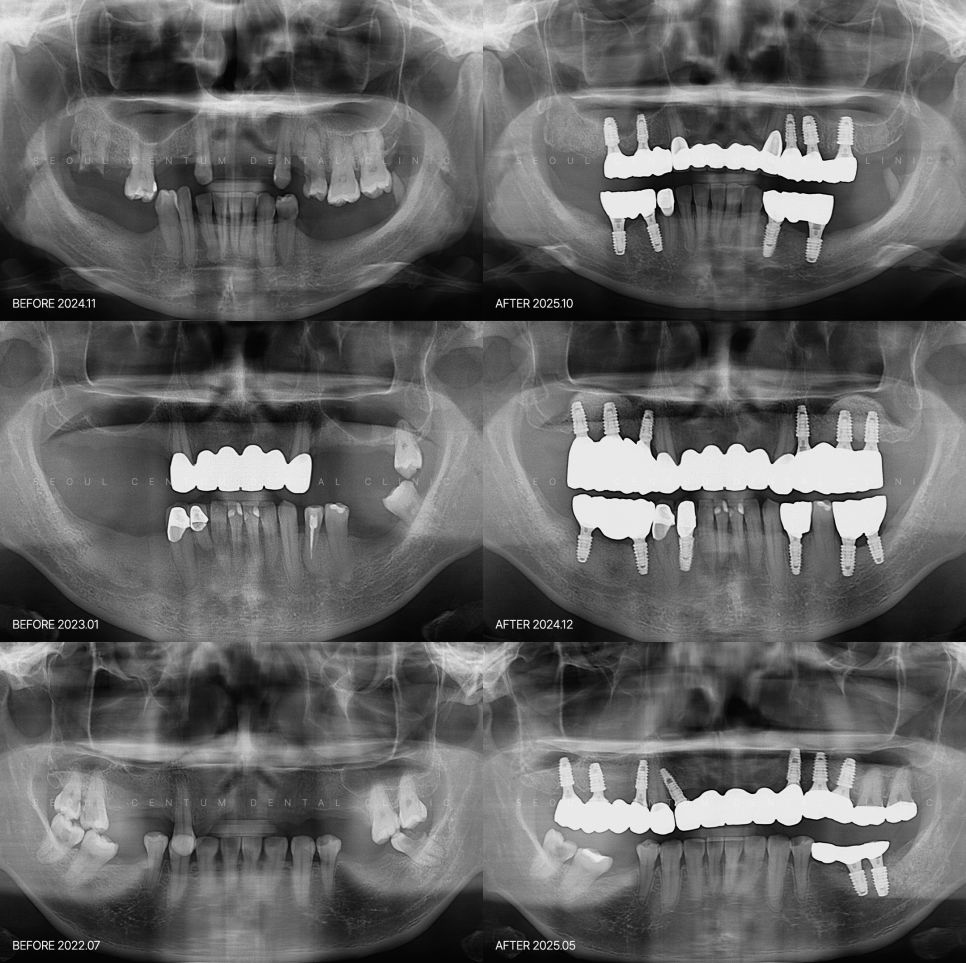

다수 식립하기 전에 알아야 할 주요사항들 여러 개의 치아가 상실되었거나 잇몸병, 파절, 노화들로 치아가 흔들려 치열 회복이 필요할 때 전체임플란트를 선택할 수 있는데요. 부분 임플란트와는 구조, 난이도, 설계가 달라 치료 과정에서 고려해야 하는 요소가 많아요. 턱뼈의 강도라던가 잇몸 형태, 교합 습관 등을 분석해야...

다수 식립하기 전에 알아야 할 주요사항들

여러 개의 치아가 상실되었거나

잇몸병, 파절, 노화들로 치아가 흔들려

치열 회복이 필요할 때

전체임플란트를 선택할 수 있는데요.

부분 임플란트와는 구조, 난이도, 설계가 달라

치료 과정에서 고려해야 하는 요소가 많아요.